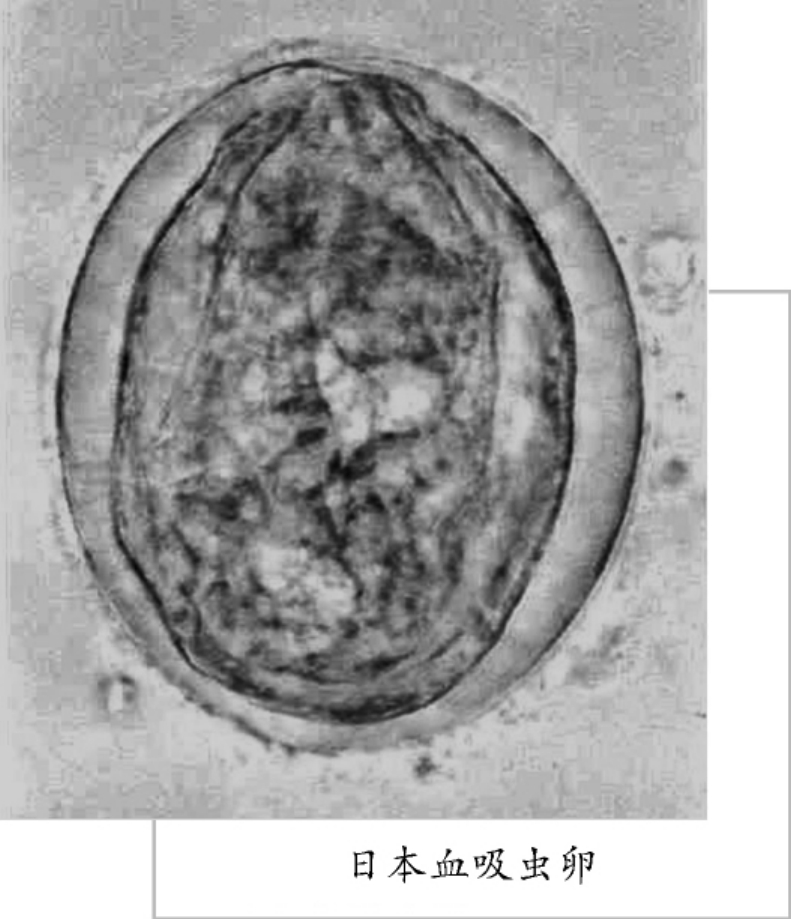

日本血吸虫

日本血吸虫在国内分布于南方各省区,国外分布在日本。

日本血吸虫小型个体,雄虫长12~24毫米,宽0.5~0.55毫米,体表基本光滑或仅有极小的棘。睾丸7个,排为一行;雌虫有卵巢1个,长圆形。子宫颈长,其中含有50个以上的虫卵。体呈紫色。

日本血吸虫成虫寄生于人或其他哺乳动物的肠系膜静脉中,雌雄虫经常抱在一起。雌虫产卵于肠壁,随粪便排出体外,在水中孵出毛蚴,如遇钉螺则侵入其体中,毛蚴在钉螺体内经过无性生殖,产生大量的尾蚴。尾蚴自螺体内逸出后,借尾部摆动,遇到人或易感染的动物而从皮肤钻入,引发感染。其寄生能引起人和动物的血吸虫病。应积极预防,大力灭螺,以免感染。

吸虫病是由血吸虫寄生于人体引起的地方性寄生虫病。寄生于人体的血吸虫主要有3种:即流行于非洲北部的埃及血吸虫;流行于拉丁美洲及非洲中部的曼氏血吸虫以及流行于亚洲的日本血吸虫。在我国因只有日本血吸虫病流行,故通常将日本血吸虫病简称为血吸虫病。日本血吸虫病在我国长江流域和长江以南13个省、直辖市、自治区严重流行,解放初期估计有患者千余万人。是我国危害最严重的寄生虫病。解放后政府开展了大规模的防治工作,流行情况得到基本控制。